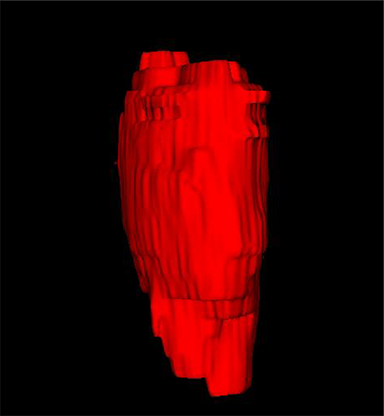

Comparison with ground truth. Some predicted results of MMFNet are shown in 2D images and 3D images in Figure 7 and Figure 8. As shown in these figures, although the shape and size of NPC are varied from each other, MMFNet can still accurately determine the regions of NPC and obtain the accurate contours of tumors. Through analyzing 2D images in figure 7, MMFNet has a capacity to fuse multi-modality MRI to reduce the confusion brought by intensity’ similarity between nearby tissues and NPC. The values of , and of MMFNet are shown in Table 1. MMFNet can reach the best results with , and .

Comparison with related works. Table 1 reports the values of , and for different methods. Predicted masks of different methods are illustrated in Figure 9 and Figure 10, which respectively present results in 2D and 3D images. Through comprehensively analyzing these results, the proposed MMFNet actually have the following properties: